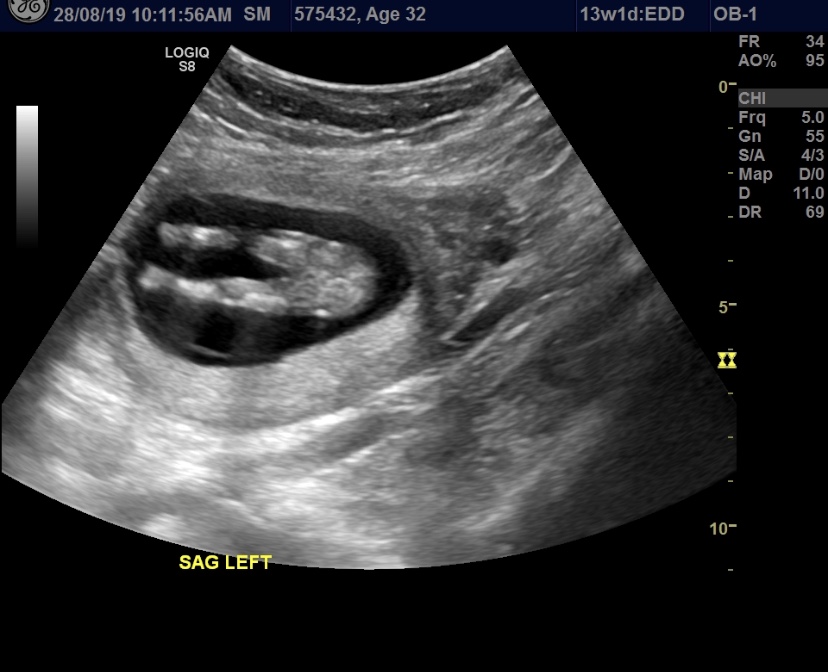

Hi Guy, would love it if you could tell me if my babe is a boy or girl. Thanks! Attachment 41923Attachment 41924Attachment 41925

Pink lean, but potty shots are not reliable for guessing at this point and that's not a clear nub.